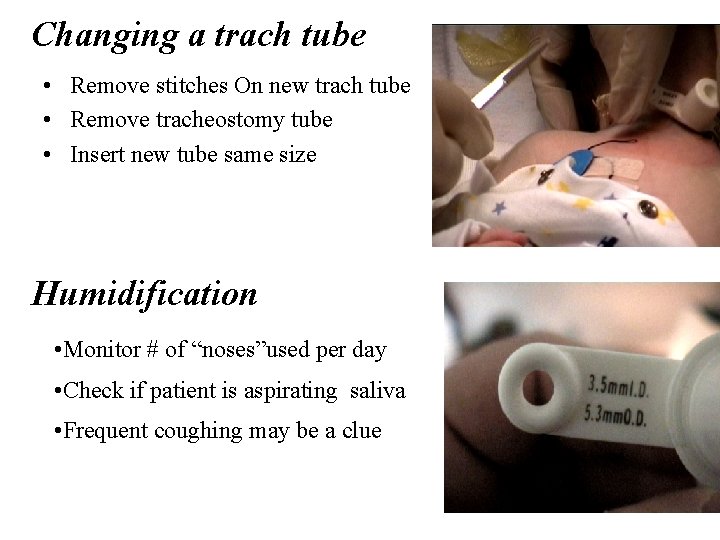

Changing a trach tube • Remove stitches On new trach tube • Remove tracheostomy tube • Insert new tube same size Humidification • Monitor # of “noses”used per day • Check if patient is aspirating saliva • Frequent coughing may be a clue